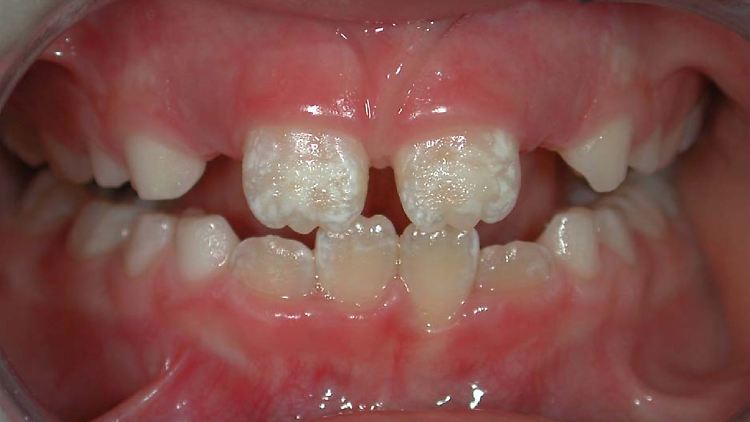

Hier deutlich zu sehen: weißlich-gelbe Flecken auf den oberen Schneidezähnen. Sie sind von einer MIH betroffen.

(Foto: Maurizio Procaccini et al/Wikipedia/CC BY 2.0)

Knapp ein Drittel aller Zwölfjährigen in Deutschland ist betroffen: Ihre Zähne sind frei von Karies und doch hat mindestens ein Zahn weiße oder gelblich-braune Flecken, ist mitunter stark berührungsempfindlich und bröckelt, wenn es schlimm kommt, einfach weg. Die Krankheit heißt Molaren-Inzisiven-Hypomineralisation, kurz MIH. Das klingt sperrig, beschreibt aber gut, worum es geht: Nie ist das gesamte Kindergebiss von der Krankheit befallen, sondern es sind die ersten bleibenden Backenzähne, die der Zahnarzt Sechsjahrmolaren nennt, sowie die oberen Frontzähne, die Inzisivi. Der Grund für die Beschwerden ist, dass im Zahnschmelz dieser Zähne Mineralien fehlen – daher Hypomineralisation.